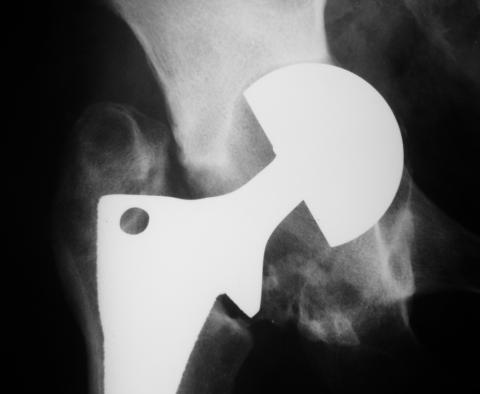

Лечился в стержневом аппарате по месту жительства. АВФ демонтировали через полгода из-за воспаления в области стержней (рис 2). После демонтажа в течение месяца больной лихорадил до 38*, были боли в бедре. Эти явления исчезли после курса антибиотиков. Через год после травмы в ЦРБ ему имплантировали биполярный протез (рис 3). Рана зажила первично. Ходил с костылями, слегка приступая на ногу. На контрольных осмотрах выявлена прогрессирующая протрузия (рис 4-6).